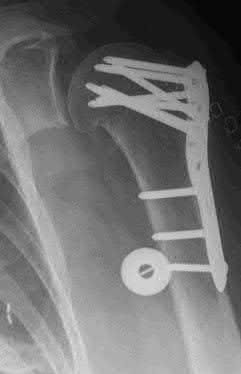

A 64-year-old woman is thrown off a horse, sustaining the injury shown in Figures A and B. She undergoes surgical fixation as seen in Figures C through E. What is the most commonly reported complication of this procedure?

The patient in the scenario has a 2-part proximal humerus fracture treated with a locking plate as seen in Figures A-E. The most common complication with the use of this implant is screw penetration. The terms screw cut out and penetration are often used interchangeably in the literature with cut out appearing more frequently in reports regarding intertrochanteric fractures.

Owsley et al retrospectively reviewed 53 proximal humerus fractures treated with locking plates and the same post-operative protocol. The most common complication was screw cut out or penetration, followed by varus displacement. They concluded that 3 and 4-part fractures in patients over 60 years have a higher incidence of failure.

Agudelo et al retrospectively reviewed 153 patients at a level-one trauma center treated with proximal humerus locking plates, investigating modes of failure for the implant. They determined that varus malreduction (head-shaft angle